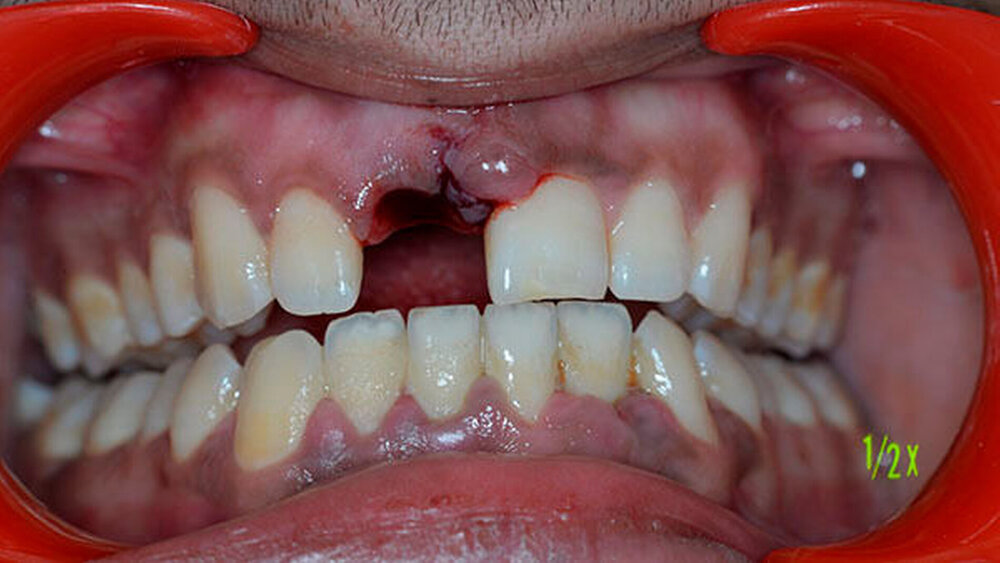

Der Patient hatte Glück im Unglück: Er fand den Zahn im Schnee. Und wickelte ihn sorgfältig in ein Papiertaschentuch. Dann transportierte er ihn unter für das desmodontale Gewebe ungünstigen Bedingungen in die Praxis.

Der Zahn wurde zwei Stunden nach dem Unfall vital replantiert und semipermanent geschient. Die anschließende Abdrucknahme erfolgte unter allergrößter Sorgfalt. Die laborgefertigte Tiefziehschiene schließt die Bereiche der semipermanenten Schiene bis zum Schienenäquator mit ein. Was die Reanastomosierung der Gefäße und Nerven betrifft, ist der Behandler zuversichtlich, reagieren doch auch vital transplantierte Weisheitszähne nach einigen Wochen wieder auf Kältereize.